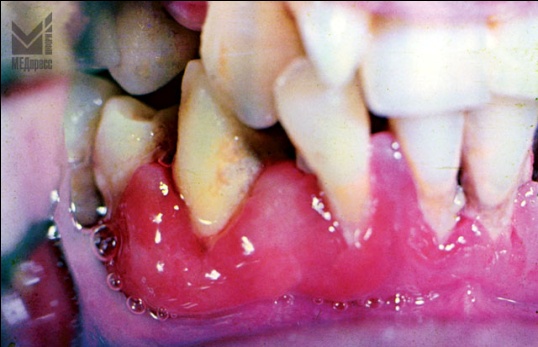

| Рис. 1. и 2. Десневой край и десневые сосочки отечны, рыхлые, имеют цианотичный оттенок. Имеются пародонтальные карманы с выбухающими грануляциями и гнойным отделяемым. Отложения зубного камня. Оголение корней зубов. Зубы подвижны. (14 и 16 лет). |